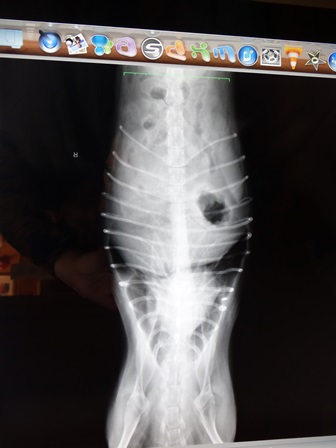

レントゲンと、エコー検査をしてもらったようです

![rnn1-00-3[1].jpg](https://image.space.rakuten.co.jp/d/strg/ctrl/9/07839b896ed5c0c25dead4e7656748aff698f28e.33.2.9.2.jpeg)

3枚目の写真・・・肺がちょっと白くボワッとしているようだけど

ホントはへそ天の万歳でレントゲンを撮れるといいけど

ヘソ天のできないトレジャーは、うつぶせの万歳だったからだろう・・・・とのこと

1枚目、2枚目で、肺、白くないからね

レントゲンと、エコーで見られるものは限られるけど、問題なさそう